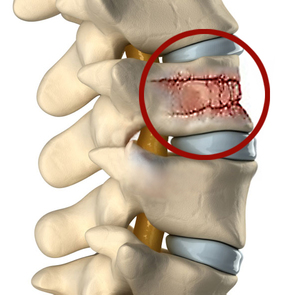

Существует три категории компрессионных переломов: первая степень — клиновидный, вторая — разрушение и третья — разрыв. Наиболее часто встречающимся типом компрессионной травмы является клиновидный перелом, который относится к первой степени.

Этот перелом характеризуется разрушением передней части тела позвонка, в результате чего кость приобретает клиновидную форму.

Перелом первой степени является наиболее распространенным вариантом компрессионного повреждения. Обычно он возникает в передней области цилиндрического позвонка, что приводит к разрушению передней части позвонка, в то время как задняя часть остается целой, что и формирует клиновидный контур. Клиновидный перелом, как правило, считается механически стабильным, однако в некоторых случаях он может вызывать деформацию позвоночника, например, в виде горбатой осанки.